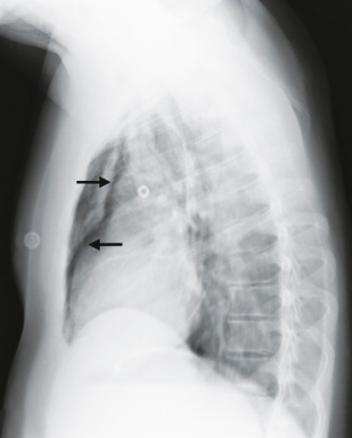

Un homme de 25 ans, sans autre antécédent qu’un tabagisme actif, a ressenti, au décours d’un repas, une douleur cervicale accentuée par la déglutition et une sensation de gêne respiratoire. Il décrivait une atteinte rhinopharyngée peu intense avec une toux grasse depuis 48 heures. Aux urgences, son état hémodynamique n’inspirait pas d’inquiétude, avec une pression artérielle à 151/85 mmHg, une fréquence cardiaque à 90 batt/min, une saturation en oxygène en air ambiant à 95 % et une fréquence respiratoire à 20 cycles/min. Il n’existait pas de notion d’effort à glotte fermée, ni de prise de toxique. L’examen clinique a révélé une rhinopharyngite banale mais surtout un emphysème sous-cutané sus-claviculaire droit (signe de Minnigerode : présence d’air dans la région para-œsophagienne du cou). La radiographie thoracique a mis en évidence un emphysème sous-cutané ainsi qu’un pneumomédiastin (fig. 1 et 2 ). Le patient a été hospitalisé 24 heures dans un service de post-urgence pour surveillance et prise en charge de la douleur. Le scanner thoracique, réalisé le lendemain, a confirmé un pneumo-médiastin de faible abondance ainsi qu’un minime pneumothorax scissural gauche (fig. 3 ). L’état de santé du patient a été réévalué en consultation de pneumologie quatre jours plus tard. L’évolution a été favorable.

Le pneumomédiastin est rare (incidence : 4/100 000) et plus encore s’il est associé à un pneumothorax (1,5 % des pneumomédiastins),1, 2 comme dans le cas de ce patient. L’augmentation de la pression dans les voies respiratoires peut être responsable de pneumomédiastin.3 L’imagerie confirme le diagnostic, notamment la radiographie thoracique. Cette pathologie, très souvent bénigne, nécessite un traitement antalgique et une surveillance simple.